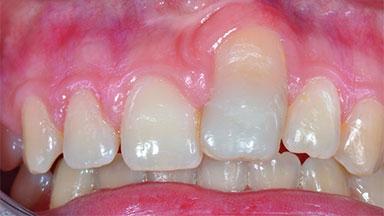

Replacement of an Ankylosed Central Incisor with a Gingival Recession: Tooth Extraction with Socket Grafting and Late Implant Placement with Simultaneous Contour Augmentation

In 2008, a healthy 15-year-old female, non-smoking patient presented at our clinic with a major esthetic problem of tooth 21. Her dental history revealed that the tooth had been avulsed by trauma years before. As a result, the replanted and temporarily splinted tooth had ankylosed and was in severe apical malposition. The ankylosed tooth exhibited a significant gingival recession that disturbed the patient greatly. Due to the patient’s low age and with her skeletal growth not completed, periodic follow-up visits were scheduled to monitor the situation until the patient was old enough for implant therapy.

Soft Tissue Contour and Volume Significantly deficient